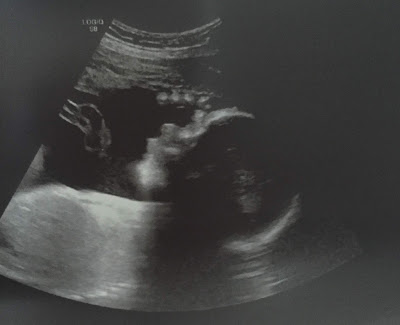

| Above: an unborn baby at 8 months (32 weeks). Graphic via the Endowment for Human Development |

32 weeks after fertilization (34 weeks LMP), Baby Chris is 17 ¾ inches long and weighs 4 ¾ pounds—about the size of a cantaloupe.

Lung development is particularly important this week. According to the Endowment for Human Development: “Starting at 32 weeks, true alveoli (al-ve’o-li), or air “pocket” cells, begin forming from alveolar ducts. Development of alveoli continues through birth and until about 8 years of age.”